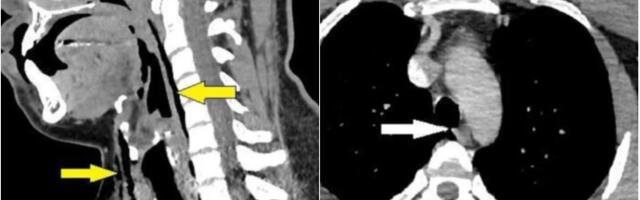

Probušio rupu u dušniku pokušavajući da spreči kijanje

Jedan čovek uspeo je da pokida svoj dušnik pokušavajući da zadrži kijanje, probušivši rupu za koju eksperti tvrde da je prva povreda ove vrste na svetu...